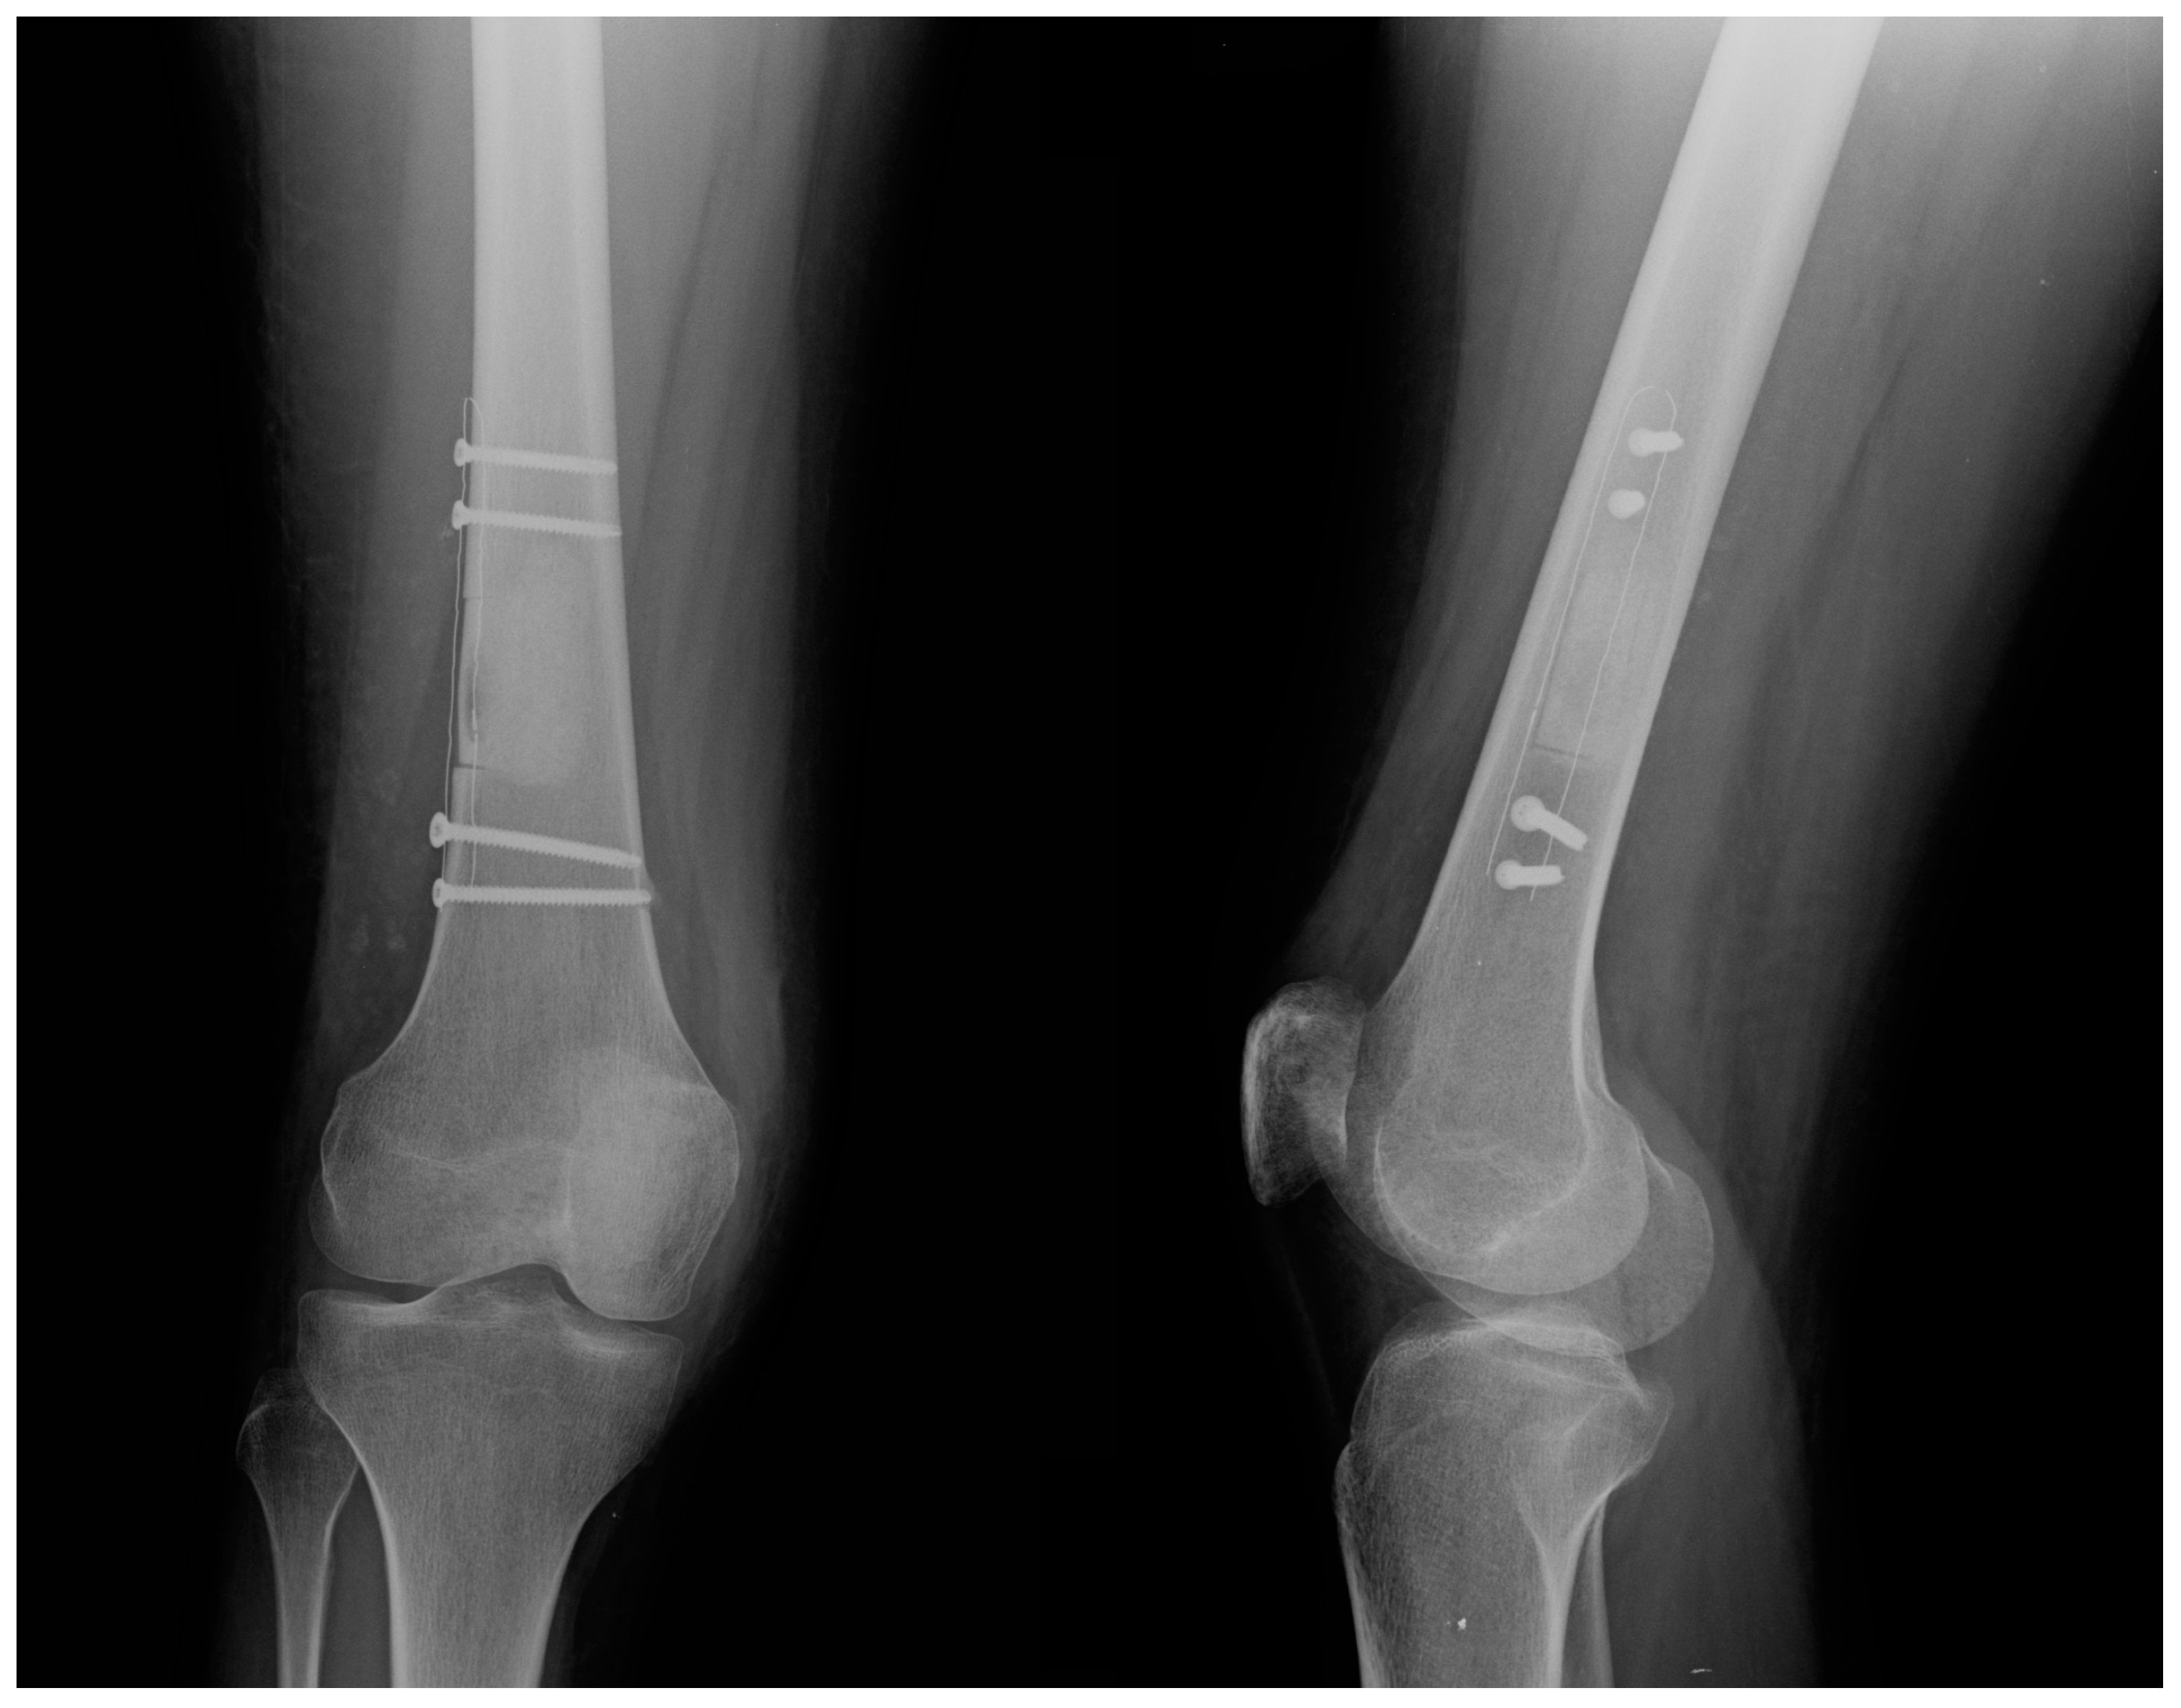

Intraoperative fluoroscopy confirmed the complete removal of the neoplastic mass, the adequate filling with the augment of choice, and the correct positioning of the fixation devices. An X-ray was also taken at the end of each surgical procedure (Figure 3).

Figure 3. Postoperative anterior–posterior (left) and lateral (right) view of a distal femur treated with curettage, bone grafting, and stabilization using a carbon-PEEK plate.